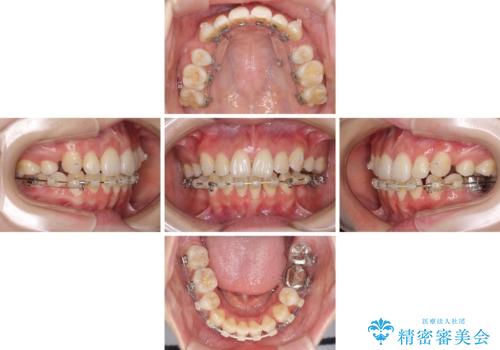

- ハーフリンガル

- 4年6ヶ月

裏側矯正特有の抜歯スペースに前後の歯が倒れ込む状態が長く続き、改善に長期間を要しました。